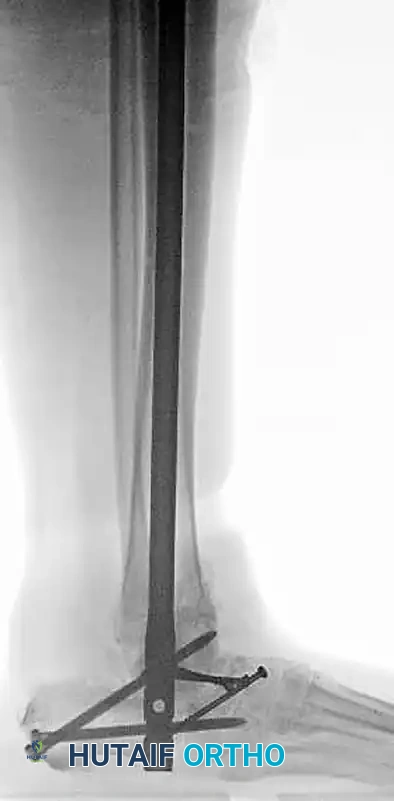

External Fixation

In cases of severe soft tissue swelling, gross instability post-reduction, or open injuries requiring serial debridement, spanning external fixation is the treatment of choice. A delta frame or a medial spanning fixator (tibia to first metatarsal and calcaneus) maintains length, alignment, and joint congruity while allowing access for wound care.

Application of a spanning external fixator to hold the reduction and stabilize the soft tissue envelope in a severe open dislocation.

Salvage tibiocalcaneal arthrodesis utilizing a retrograde intramedullary nail and femoral head allograft for a patient with severe post-traumatic talar AVN and collapse following an open dislocation.